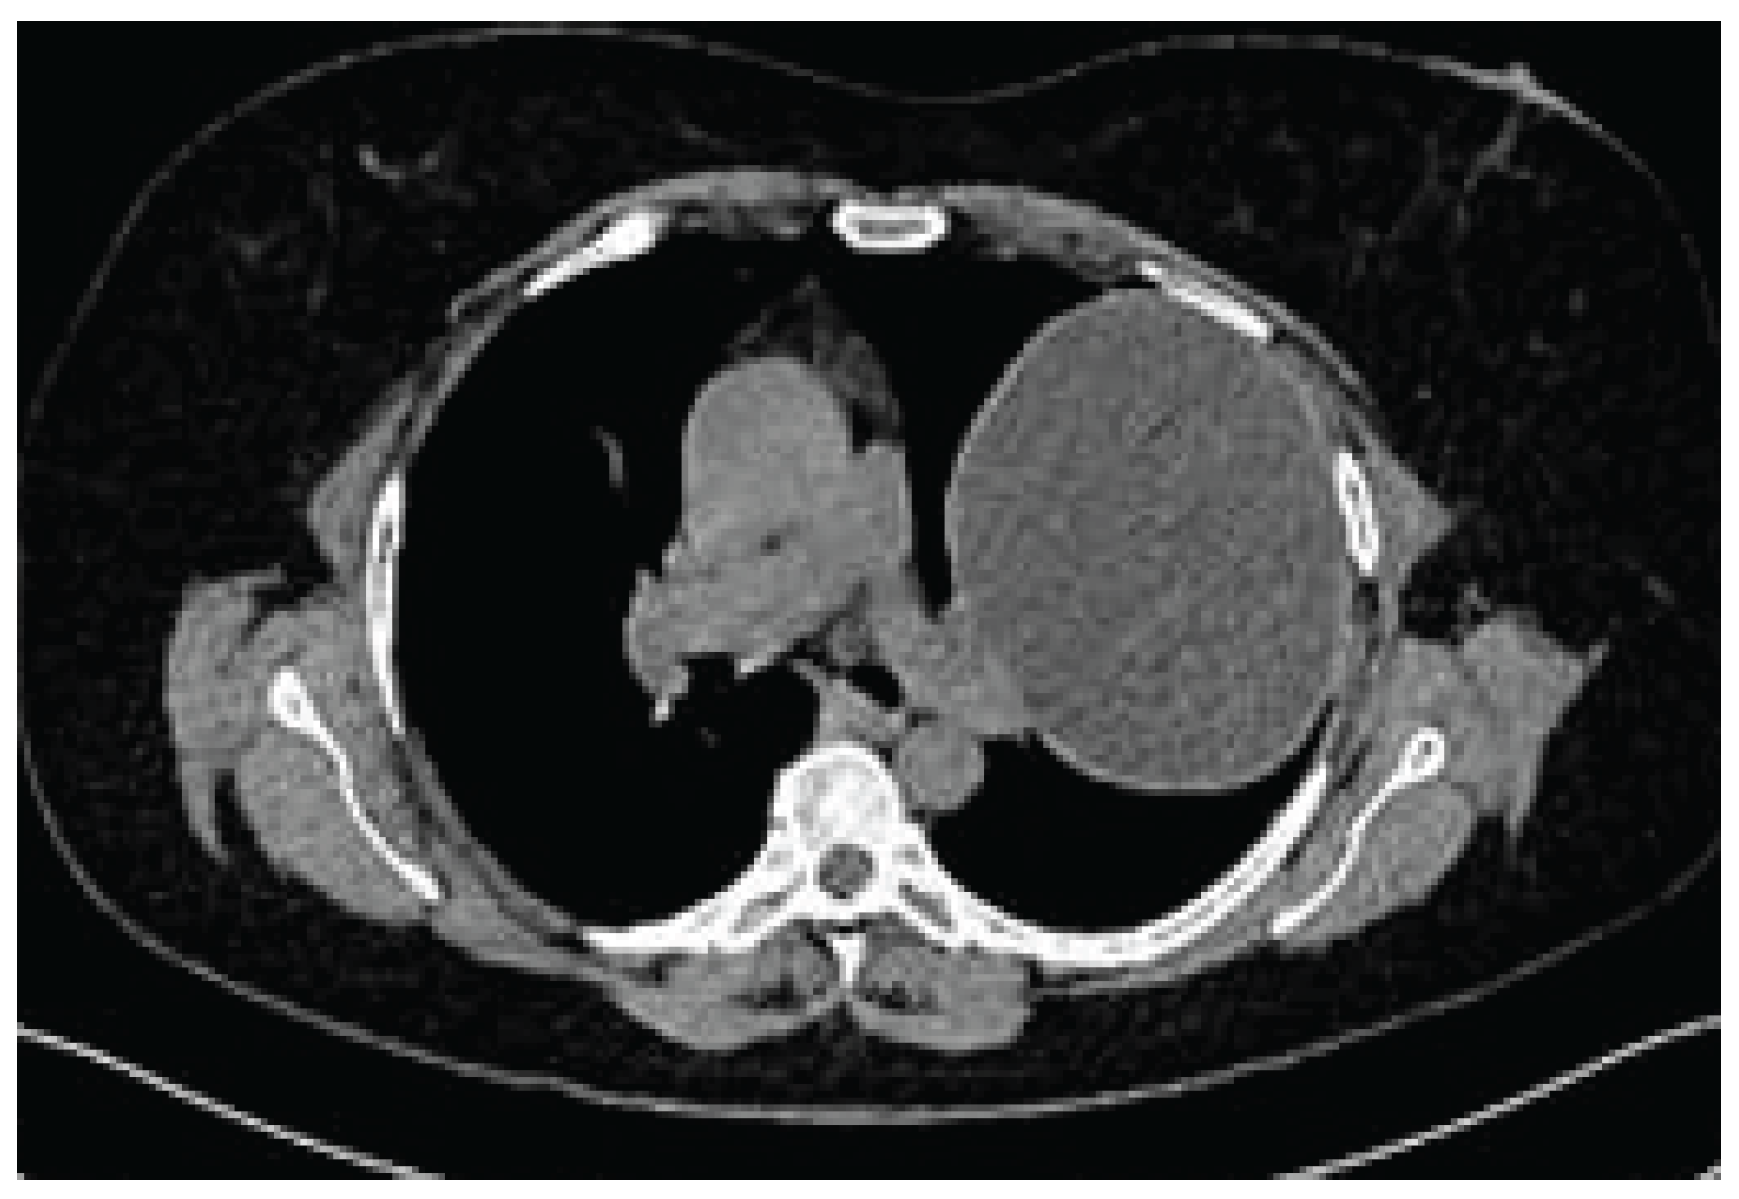

Case